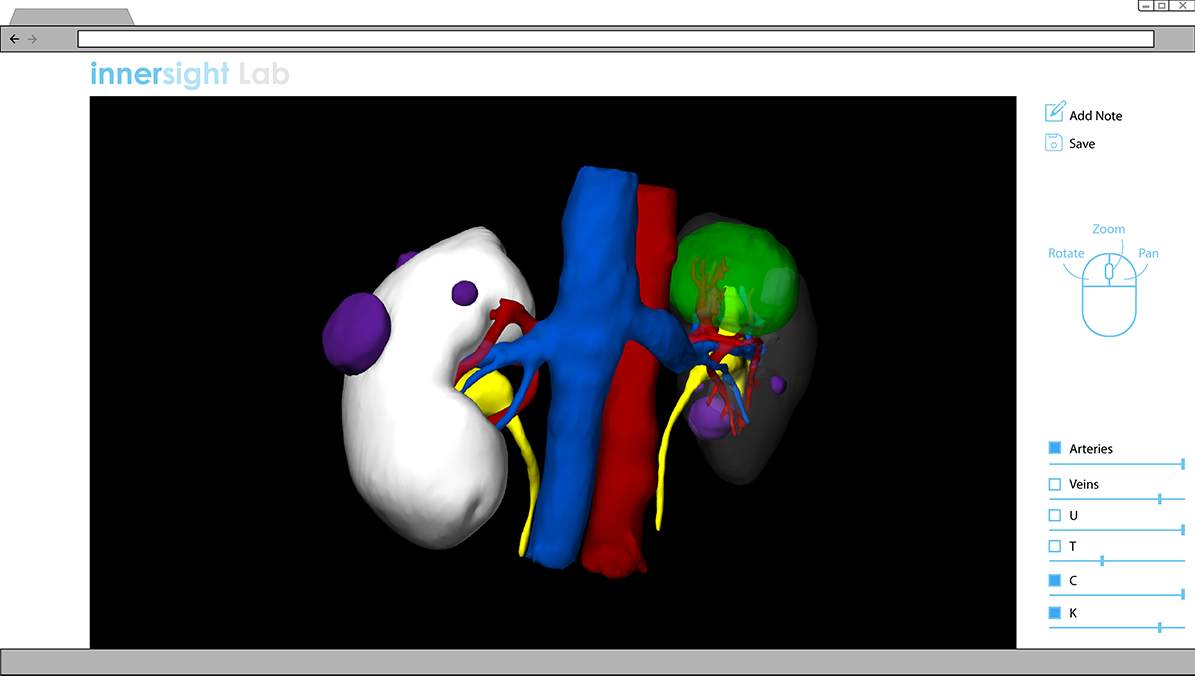

Proposed Interface for 3D models

In my proposal, the functionality of controlling the visibility and transparency of different components are made visible right away. They are placed at the bottom right corner of the screen for easier interaction, catering to the large majority of people who are right handed. Visibility of different components can be switched on and off by clicking on boxes, while transparency is controlled via the slider. It additionally proposes the functionality of adding notes and saving a specific view, for ease of referring back to it later. The proposed layout eliminates the need for existing pop up windows, which significantly reduces the number of clicks needed.

Functionalities of rotating, zooming and panning are concisely explained by the mouse icon. The intention is for it to disappear after some time, once users become familiar.